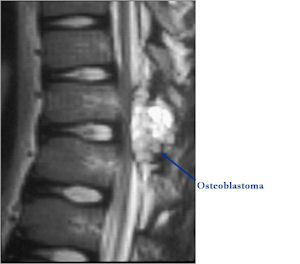

MRI:

- Also useful in determining extent

- There is often extensive edema around the tumor in the surrounding bone and soft tissues that can lead to a misdiagnosis of a malignant tumor.

Osteoblastoma